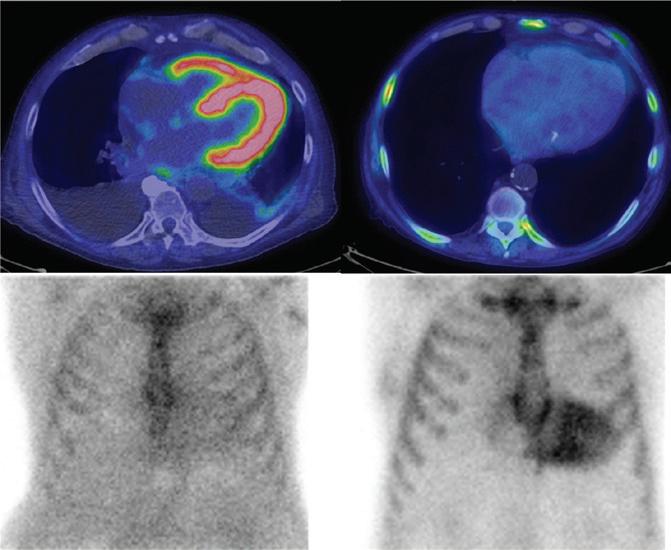

Imaging in Heart Failure with Preserved Ejection Fraction: A Multimodality Imaging Point of View

Serkan Ünlü, Özge Özden and Ahmet Çelik

Role of Imaging in Cardiomyopathies

Vincenzo Castiglione, Alberto Aimo, Giancarlo Todiere, Andrea Barison, Iacopo Fabiani, Giorgia Panichella, Dario Genovesi, Lucrezia Bonino Alberto Clemente, Filippo Cademartiri, Alberto Giannoni, Claudio Passino, Michele Emdin and Giuseppe Vergaro

DOI: https://doi.org/10.15420/cfr.2022.26